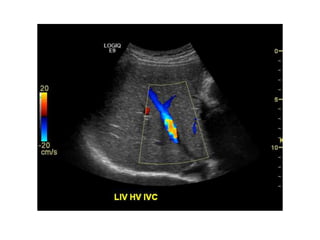

Doppler modes

Color Flow (CF)

A Primer ofDiagnostic Ultrasonic Imaging Modalities Doppler modes: Color Flow (CF) Spectral Doppler

A Primer ofDiagnostic Ultrasonic Imaging Modalities Doppler modes Color Flow (CF)